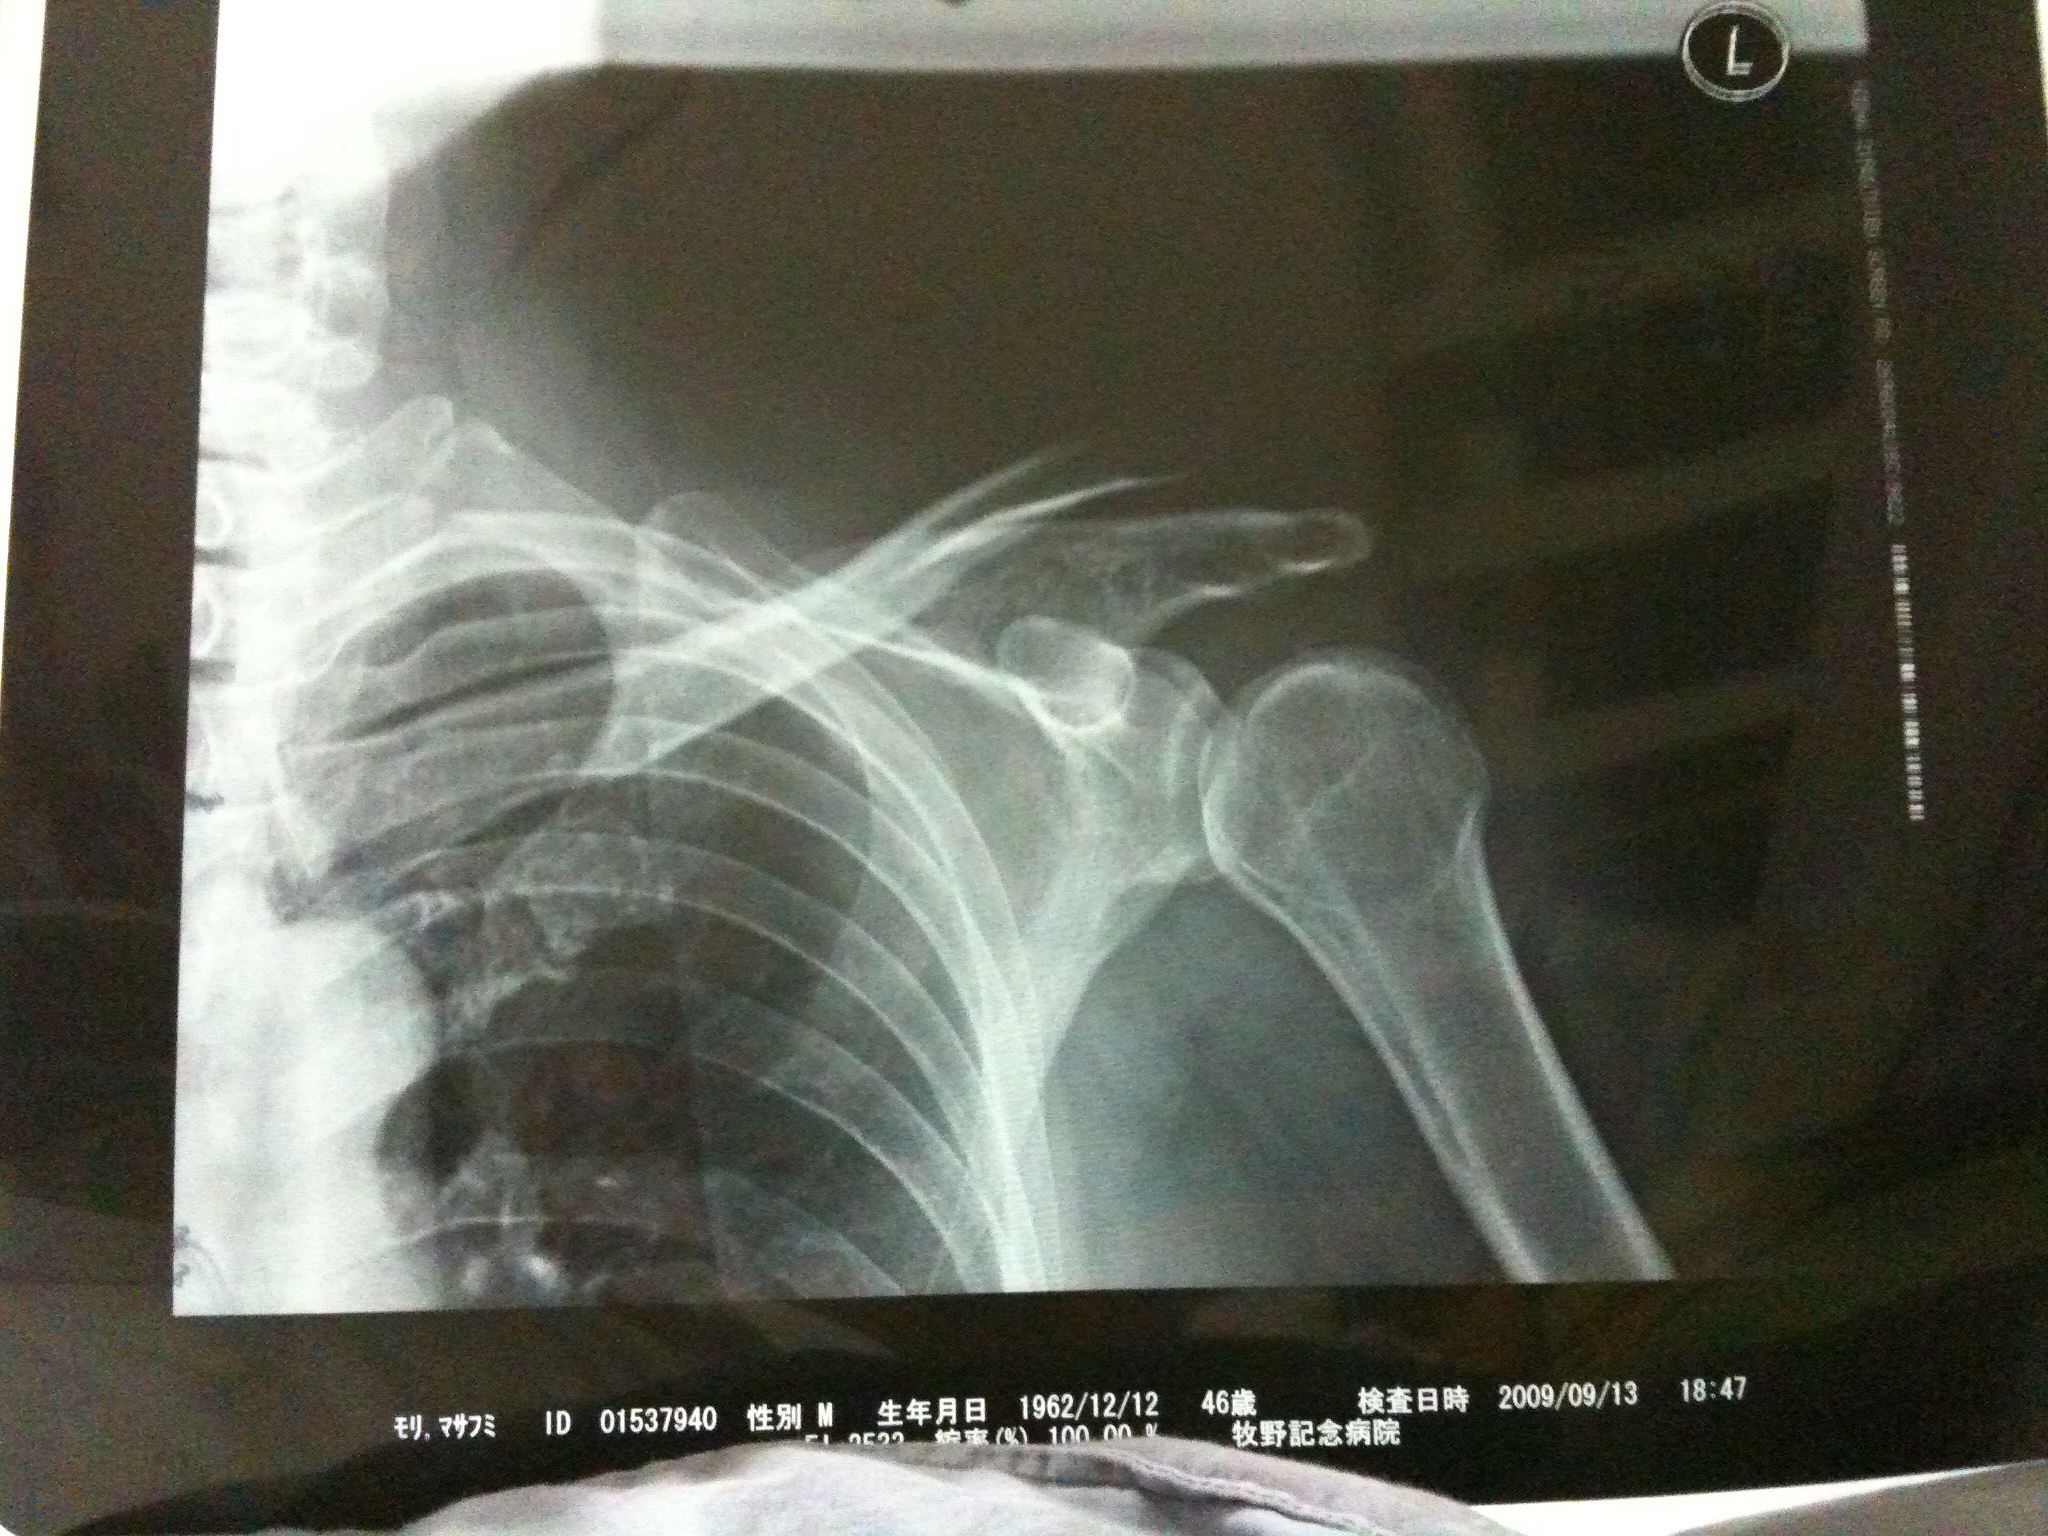

レントゲンを撮ると、

骨が飛び出してます。

お医者さん曰く、

「肩の靱帯が全部バラバラだから、明日緊急手術かもしれません」